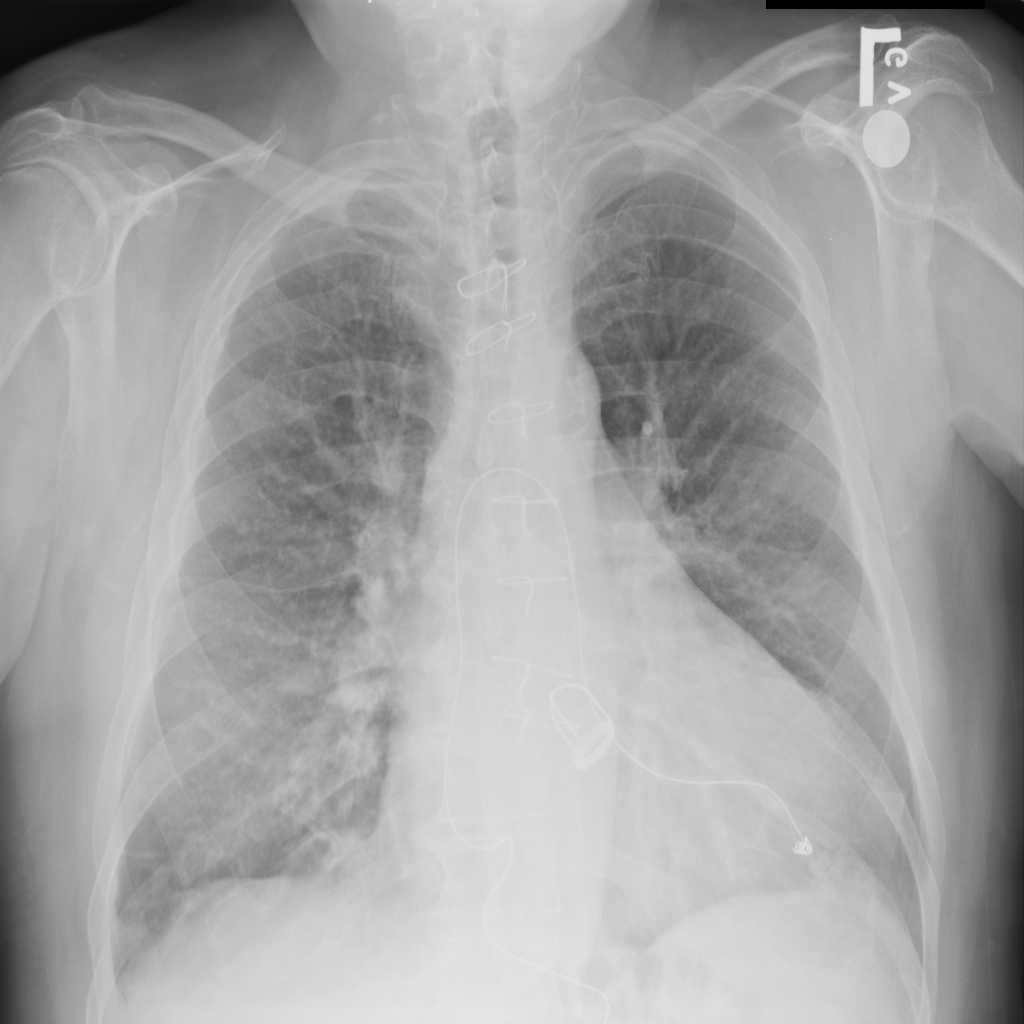

Showing up to 90 reference images for Cardiomegaly.

PAT-AE5C · IMG-000Cardiomegaly

PAT-AE5C · IMG-000

PA